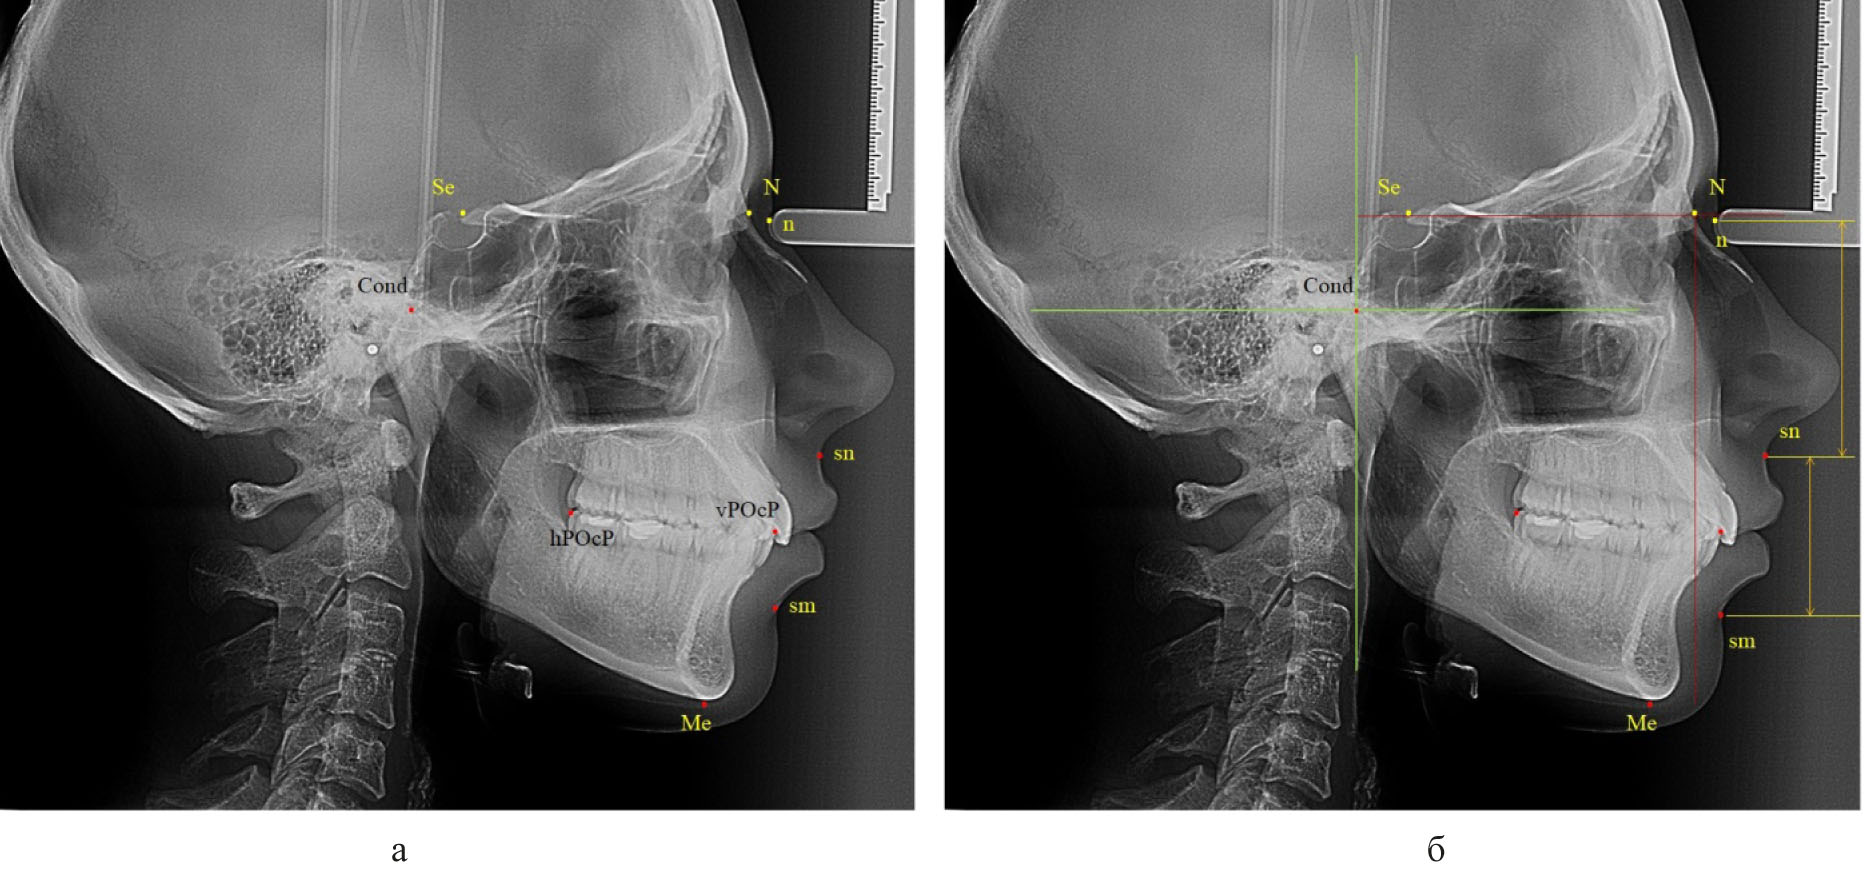

Далее проводили построение суставного круга, радиусом которого было расстояние от точки «Cond» до задней окклюзионной точки «hPOcP» (рис. 3).

Рис. 3. Основные точки (а) особенности построения суставного круга и диагностических линий (б) для построения окклюзионной плоскости

Следует отметить, что окружность пересекала линию «Cond-Mx» и делила ее на два неравных отрезка. При этом расстояние от точки «Cond» до пересечения с окружностью было в 1,5 раза меньше размера «Cond-Mx», что может быть использовано в качестве ориентира построения суставного круга при отсутствии зубов жевательных сегментов или при аномалиях положения вторых моляров.

Касательная линия к нижней части суставного круга, проведенная из точки мандибулярного ориентира «Mn», как правило, была параллельна окклюзинной линии вне зависимости от типологических особенностей роста лица и челюстных костей.